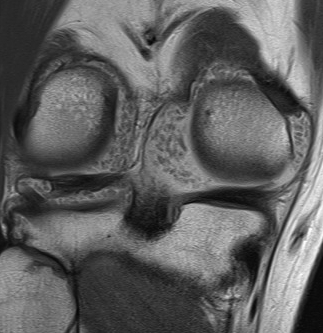

Results PVNSDefinition

Pigmented Villo-Nodular Synovitis - benign inflammatory process that arises in synovial tissues - contains significant amounts of hemosiderin

Epidemiology

Age: 20 - 50 Sex: M > F

Types

A. Diffuse - throughout joint synovium - more difficult to treat / excise fully